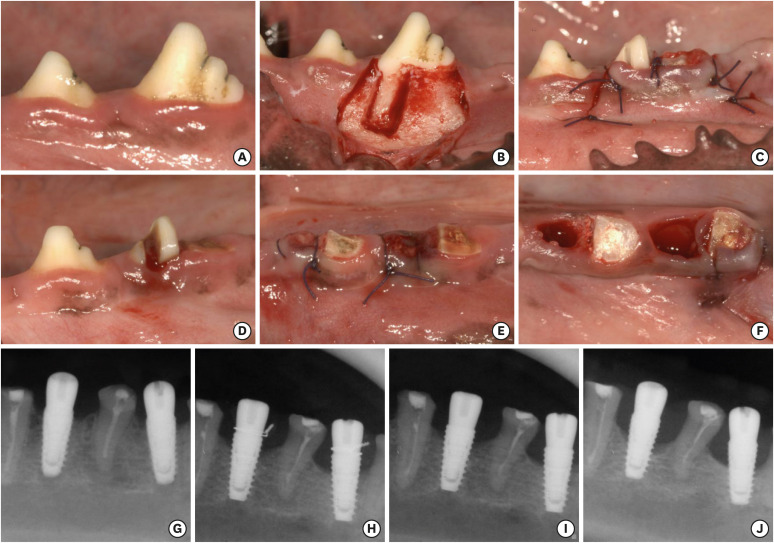

Methods: The bilateral mandibular third or fourth premolars of 6 beagle dogs were randomly assigned to 4 groups: IT/SH, IT/ARP, NIT/SH, and NIT/ARP. Following implant placement, core biopsies were retrieved from each site, and the ISQ value was measured. A 3-month period was allowed for peri-implantitis induction, followed by an additional 3 months for the spontaneous progression of peri-implantitis, with radiographs taken at each time point.